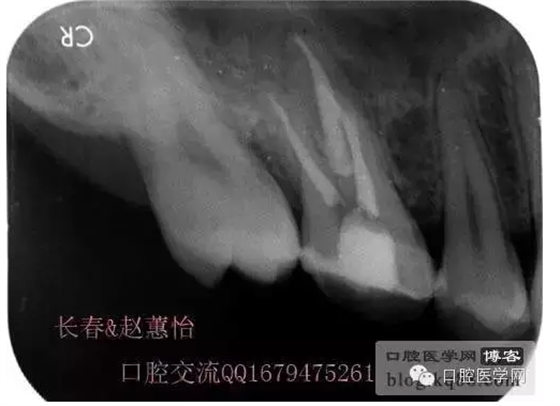

術后,明顯可見近中頰側根管臺階位置

越過臺階后小心預備直至大錐度銼可以順利進術前片的小彎沒當回事,哎